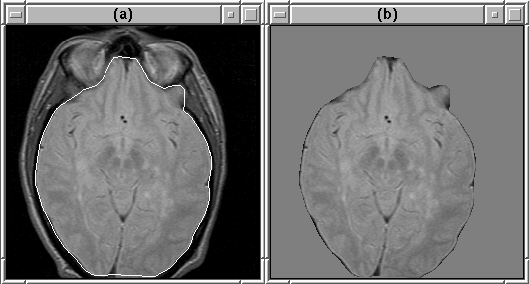

rdObj #1 inputs the brain mask produced by the Generate Final Brain Mask process and sends it to mriMaskAverage. Using the mask, mriMaskAverage finds the average intensity of brain voxels in the MR volume input by rdObj. It then assigns the average intensity to voxels outside the mask. Figure 7.19 shows the result of the masking operation.

Figure 7.19: An MR image slice (a) before masking

and (b) after. The intracranial boundary is overlaid on (a).